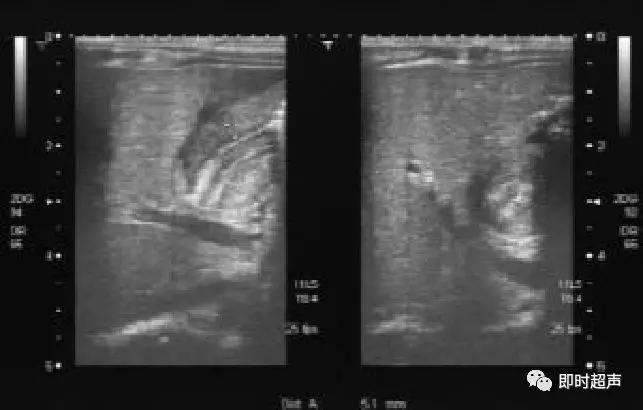

小儿阑尾炎超声诊断

超声评估标准

短轴位显示为靶环征,阑尾壁血流信号增多;长轴位显示阑尾增粗,压之不变形,管壁不均匀增厚,最大直径超过6mm。

间接征象:阑尾周围脓肿,表现为形态不规则、边界模糊的混合回声或低回声团块;盆腔/腹腔积液;阑尾周围肠系膜脂肪组织、大网膜炎性改变,表现为条带状、絮状、片状高回声围绕包裹;阑尾腔内粪石伴声影;粘连性肠梗阻、腹膜炎,肠腔减缓蠕动、相邻肠管积液积气、扩张。

超声表现:

- 增粗,外径>6mm

- 形状:“C”、“U”、“L”

- 管壁三层结构

- 粪石:声影

- 阑尾周围积液、腹腔积脓

- CDFI: 增加 缺失

阑尾炎超声声像图

腊肠征与同心圆征

包块与粪石